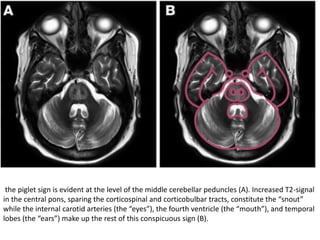

the piglet sign is evident at the level of the middle cerebellar peduncles (A). Increased T2-signal

in the central pons, sparing the corticospinal and corticobulbar tracts, constitute the “snout”

while the internal carotid arteries (the “eyes”), the fourth ventricle (the “mouth”), and temporal

lobes (the “ears”) make up the rest of this conspicuous sign (B).

Central pontine T2 hyperintensity and diffusion restriction with "trident" configuration, with

peripheral sparing, consistent with osmotic demyelination